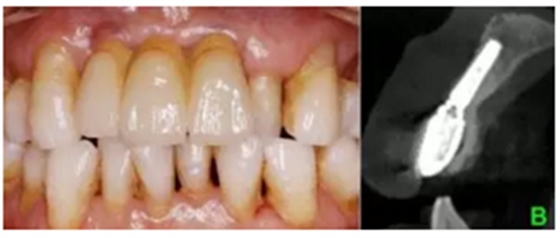

(7)修復(fù)6個(gè)月后復(fù)查

9.png

結(jié)合PRF的位點(diǎn)保存術(shù)后牙槽嵴輪廓豐滿,CBCT示骨量充足,數(shù)字化種植外科導(dǎo)板輔助下植體植入三維位置精確,種植體骨結(jié)合良好,數(shù)字化口掃系統(tǒng)數(shù)據(jù)采集高效、精確,臨時(shí)修復(fù)體戴入,軟組織成形,最終修復(fù)體戴入后穩(wěn)定、密合,牙齦軟組織色澤形態(tài)正常,美學(xué)效果良好。